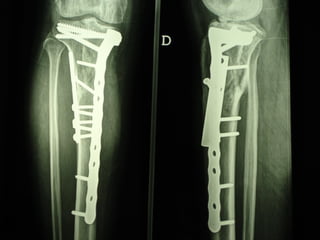

Dal Gennaio 2000 al Febbraio 2006 abbiamo trattato 167 fratture chiuse  con placca percutanea  in 164 pazienti :  27 lesioni diafisarie di gamba, 12 piloni tibiali ,  11 fratture prossimali di tibia, 36 fratture sovracondiloidee di femore, 17 fratture diafisarie di femore, 43 fratture metaepifisarie prossimali di omero, 21 diafisarie d’omero.  156 guarigioni 8 fallimenti

I buoni risultati ottenuti dipendono da 5 punti fondamentali:   una accurata riduzione percutanea della frattura  precise vie di accesso  l’utilizzo della placca che consenta il più lungo braccio di leva possibile il pretensionamento della placca  una sintesi con un ridotto numero di viti

Placche lunghe e pretensionate

Placche lunghe e pretensionate Sintesi con un ridotto numero di viti